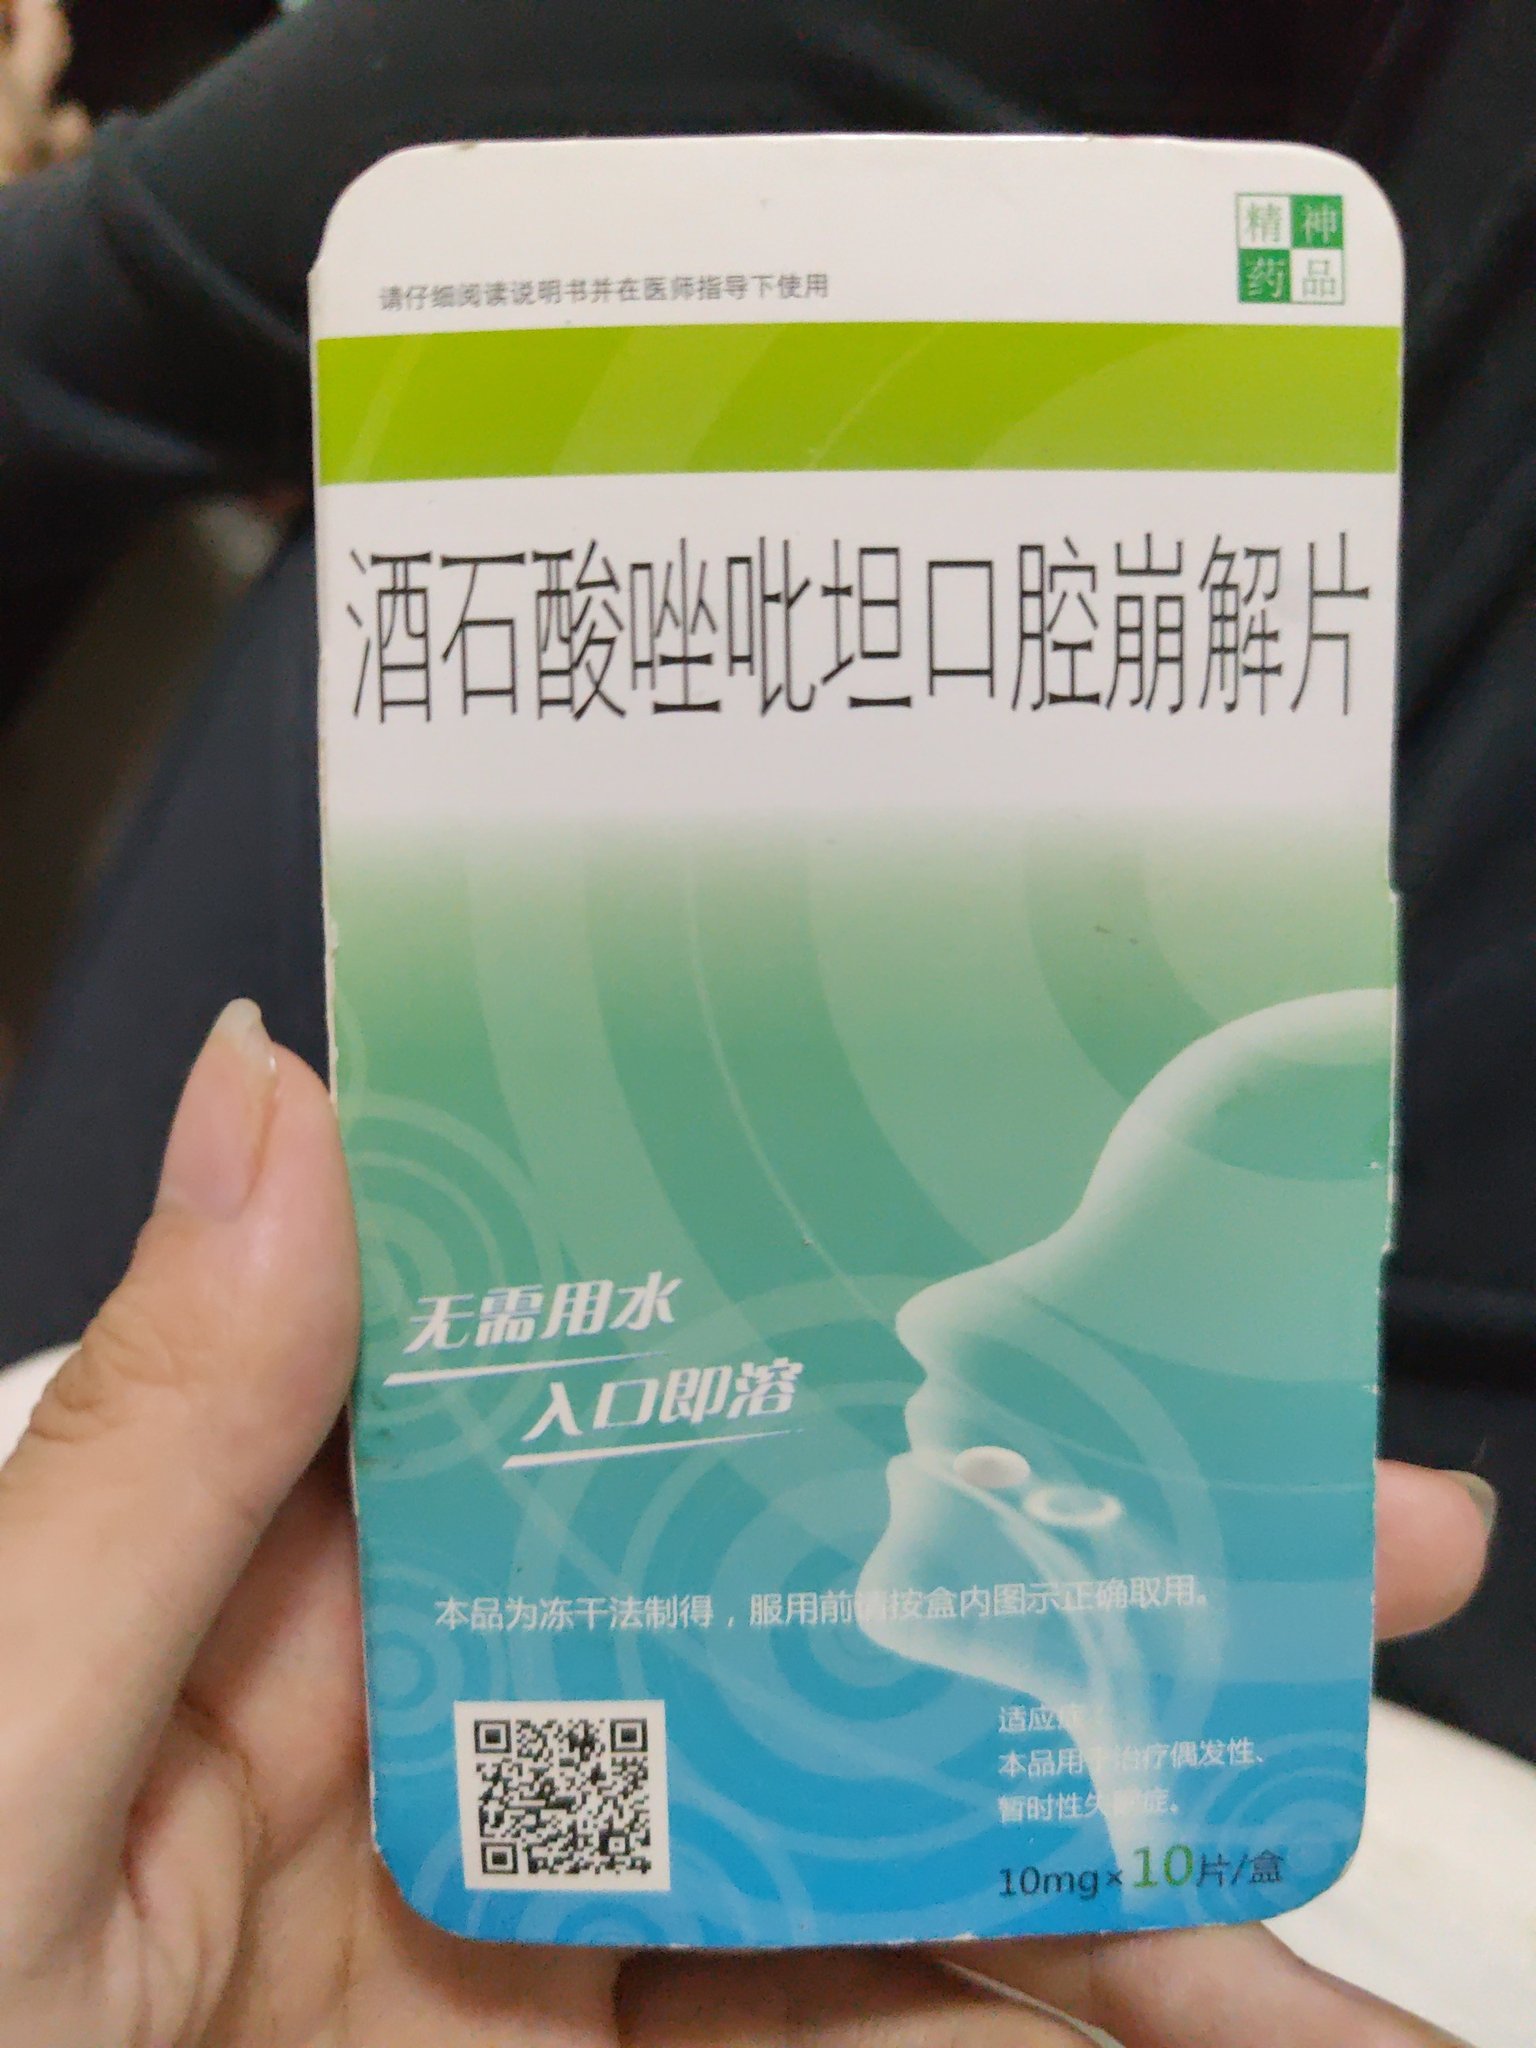

桉 @Kurokawa863905@AnIncandescence srds 酒石酸唑吡坦居然有口崩片 第一次看到诶…吃起来效果和思诺思差不多嘛

炽烈已极 @AnIncandescence@Kurokawa863905 有的。感觉起效更快一点。劣势是苦和贵